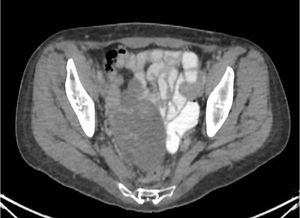

In this edition of Clinical Quandaries, Regina Barragan-Carrillo, MD, and colleagues present a case of an 18-year-old man who has a 1-month history of nonpainful right testicular enlargement.